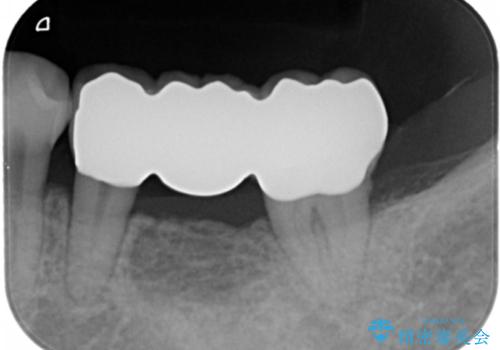

- 63.8万円 左下部分矯正27.5万円 奥歯ブリッジ36.3万円(仮歯1.1万円×3本 ジルコニアクラウン11万円x3本)費用は治療当時の料金となります

奥歯の部分矯正を行うことで、歯の傾きが良くなり、結果神経を取らずにブリッジを入れていくことができました。

通常矯正治療後は歯並びが戻らないように保定が必要ですが、ブリッジを入れているので歯並びは戻らないため保定が不要です。